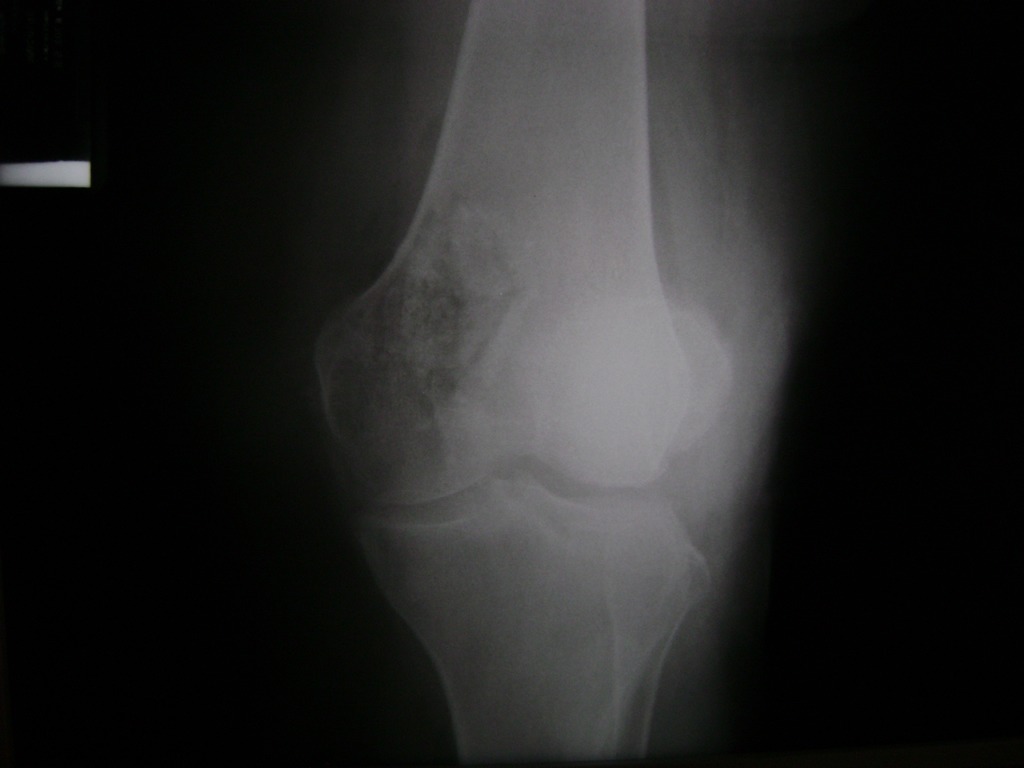

La artroscopia de rodilla es un cirugía en el cual la estructura interna de la articulación es examinada ya sea para realizar un diagnostico o para realizar un tratamiento, este procedimiento se realiza utilizando un instrumento parecido a un pequeño tubo llamado artroscopio.